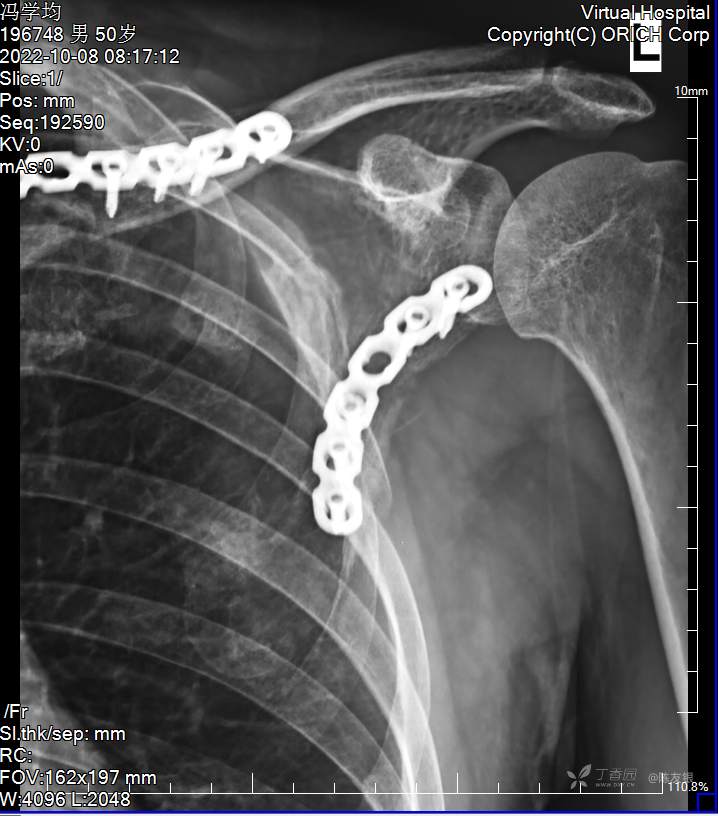

治疗经过:入院后积极完善相关检查,立即急诊在全身麻醉下行剖腹探查术+脾脏切除术+回肠部分切除术+左侧胸腔闭式引流术+左胫骨结节牵引术+多部位清创缝合术,术后给其抗休克、预防感染、输血、纠正血容量、对症治疗,待病情稳定后,2022年8月1日在全麻下行左股骨干多段粉碎性骨折切开复位髓内针、钢板内固定,左锁骨骨折切开复位内固定术,2022年8月8日在全麻行左肩胛骨骨折切开复位内固定术。术后给其预防感染、消肿止痛、活血化瘀、改善微循环、促进骨质生长、对症治疗,逐渐加强功能锻炼。术后患者切口一期愈合,逐渐康复出院。